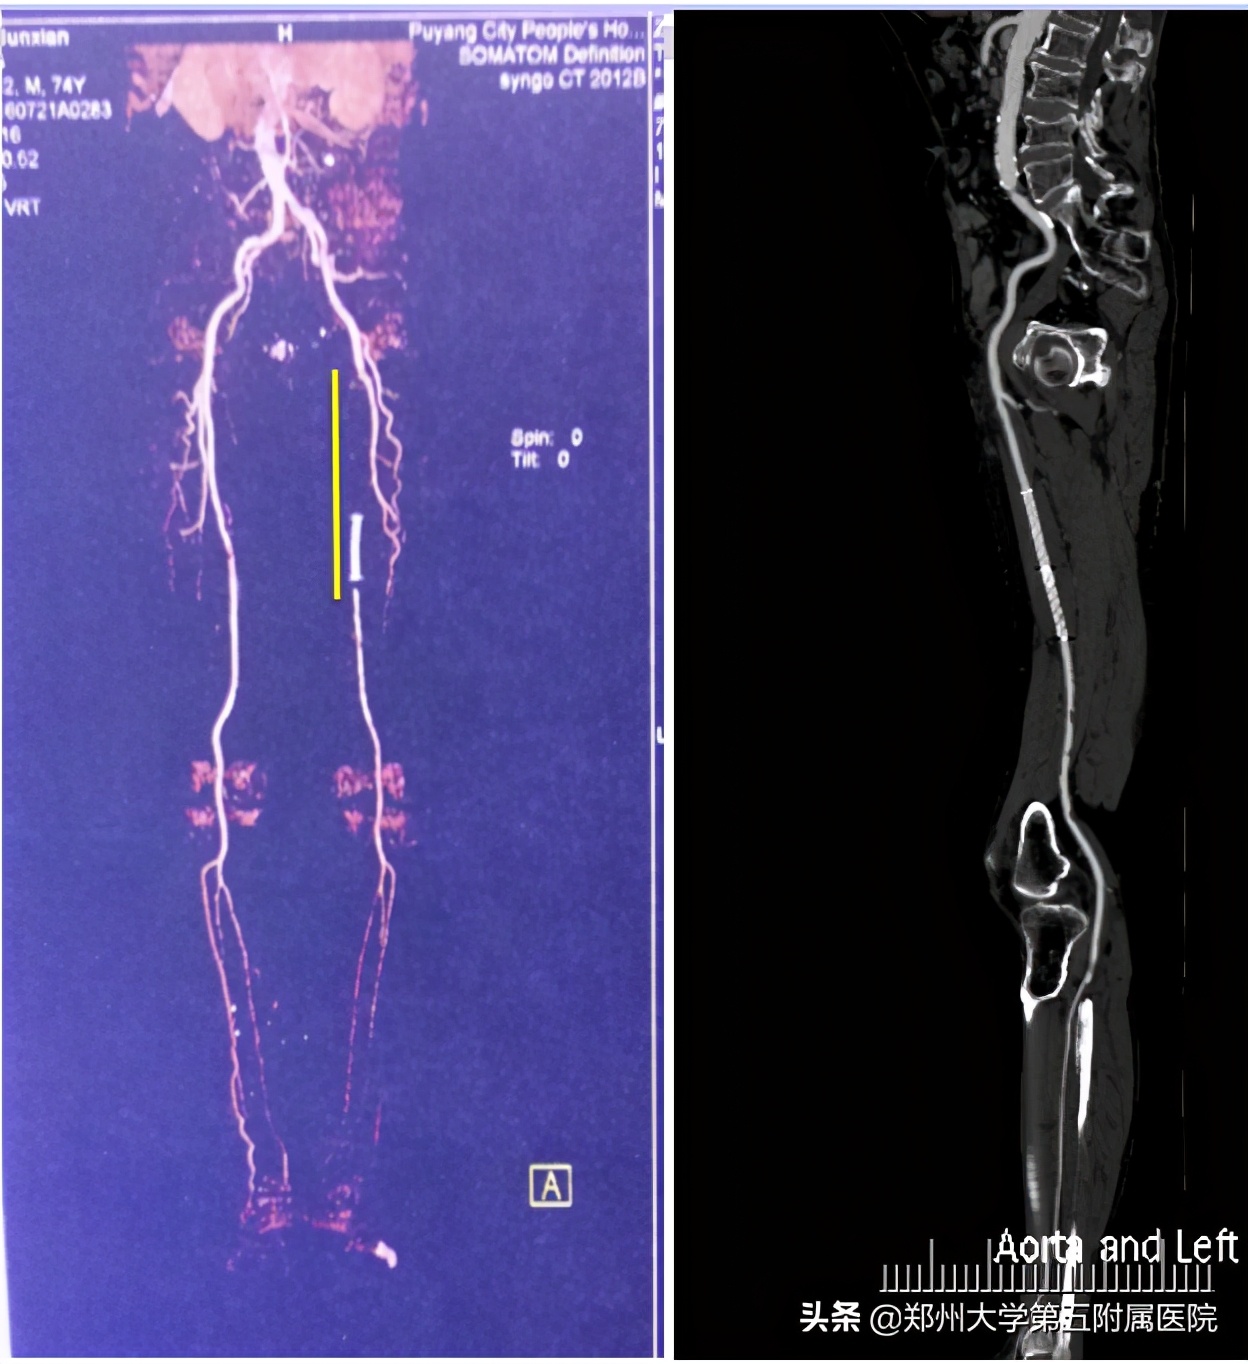

▲ 双下肢动脉多发闭塞病人,经取栓及支架植入术后,血管通畅良好